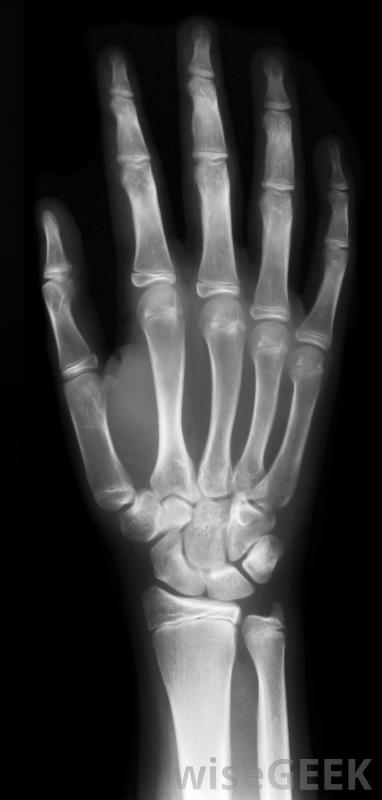

手的X光。

傳統的X光通過測量被檢測物體吸收的X光量來創建圖像。在醫療使用中,骨骼在X光片上比皮膚或器官更容易看到的原因是骨骼的成分吸收了更多的X光,檢測受檢物體的輻射反射。